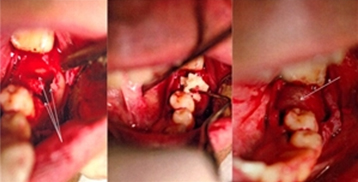

Figure 1: Patient 3. Preoperative view of tooth no. 3.6 with chronic fistulous area at the buccal bifurcation.